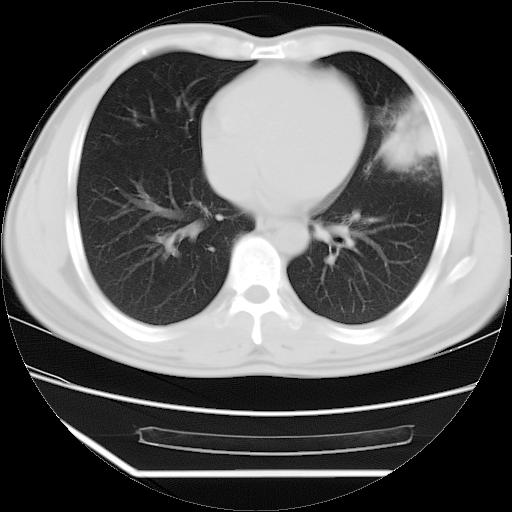

男,38岁,于2009年8月9日晚突发左侧胸痛,今x线提示左下肺阴影,为了明显确诊断,行ct检查,

血常规:嗜酸性细胞增高,单核细胞增高。

纵膈窗

病灶发生在下叶,密度均匀,边缘模糊、毛糙,周围血管纹理增强扭曲改变,靠近胸膜处病灶胸膜反应明显。

支持考虑---球形肺炎。

左肺舌叶病变。主体病灶呈类圆形中心密度低,成液化趋势周边班片影分布

考虑肺脓肿

虽然实验室检查支持炎性病变,且病变内有坏死改变(中央呈大片状低密度影),但仍不能掉以轻心,鳞癌也可以有这种影像改变。